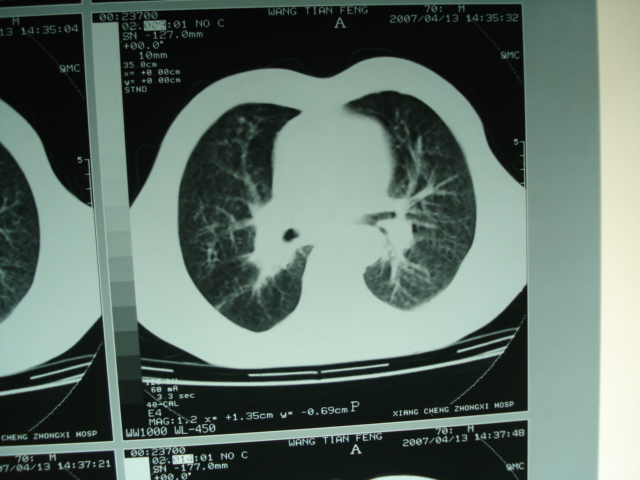

以下是引用狙击手在2007-4-18 20:17:00的发言:[br]原:2007/1/22号ct片:右肺上叶可见片状、云雾状高密度影,右肺上叶后段可见三角形高密度影,尖端指向肺门,右肺上叶后段支气管壁不规则增厚,管腔不规则增厚,纵隔未见肿大淋巴结.[br] 今ct:右肺上叶片状影增大,右肺上叶后段不张及右肺上叶后段支气管壁不规则增厚未见变化,右肺下叶背段支气管壁不规则增厚.[br] 如果考虑肺结核,但从临床证据看竟然没有一项支持肺结核,不知患者是否已经过正规抗结核治疗。没有的话,3个月了前后片看起来变化不大,似乎有不太符合肿瘤征象,不知患者是否抗炎治疗过,下叶支气管增粗还是要高度警惕,同意楼主意见,将常规病理,生化检查再做一遍。[br]

以下是引用狙击手在2007-4-18 20:17:00的发言:[br]原:2007/1/22号ct片:右肺上叶可见片状、云雾状高密度影,右肺上叶后段可见三角形高密度影,尖端指向肺门,右肺上叶后段支气管壁不规则增厚,管腔不规则增厚,纵隔未见肿大淋巴结.[br] 今ct:右肺上叶片状影增大,右肺上叶后段不张及右肺上叶后段支气管壁不规则增厚未见变化,右肺下叶背段支气管壁不规则增厚.[br] 如果考虑肺结核,但从临床证据看竟然没有一项支持肺结核,不知患者是否已经过正规抗结核治疗。没有的话,3个月了前后片看起来变化不大,似乎有不太符合肿瘤征象,不知患者是否抗炎治疗过,下叶支气管增粗还是要高度警惕,同意楼主意见,将常规病理,生化检查在做一遍。[br]